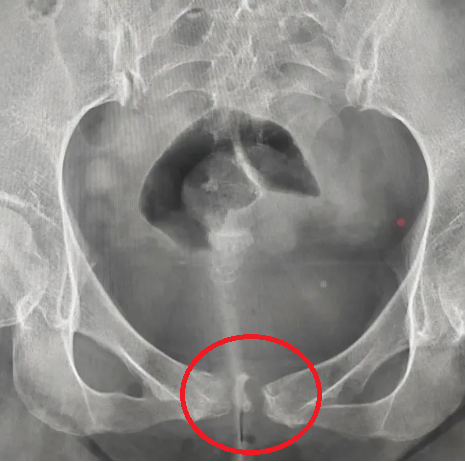

1.X线摄影检查—最简便

主要影像表现有耻骨联合间隙正常或增宽,骨缘骨质硬化,部分囊变,多见于双侧,也可单侧;耻骨联合骨缘锯齿状、鼠咬状、虫蚀状骨质破坏,边缘不光整,有时可见游离小骨块,有时耻骨联合呈不同程度错位。

2.CT扫描

相比普通X线摄片显示更清晰,除清晰显示DR片所表现外,还可显示:死骨、间隙内游离多发碎裂小骨块 、耻骨联合关节面囊变及周围软组织情况。